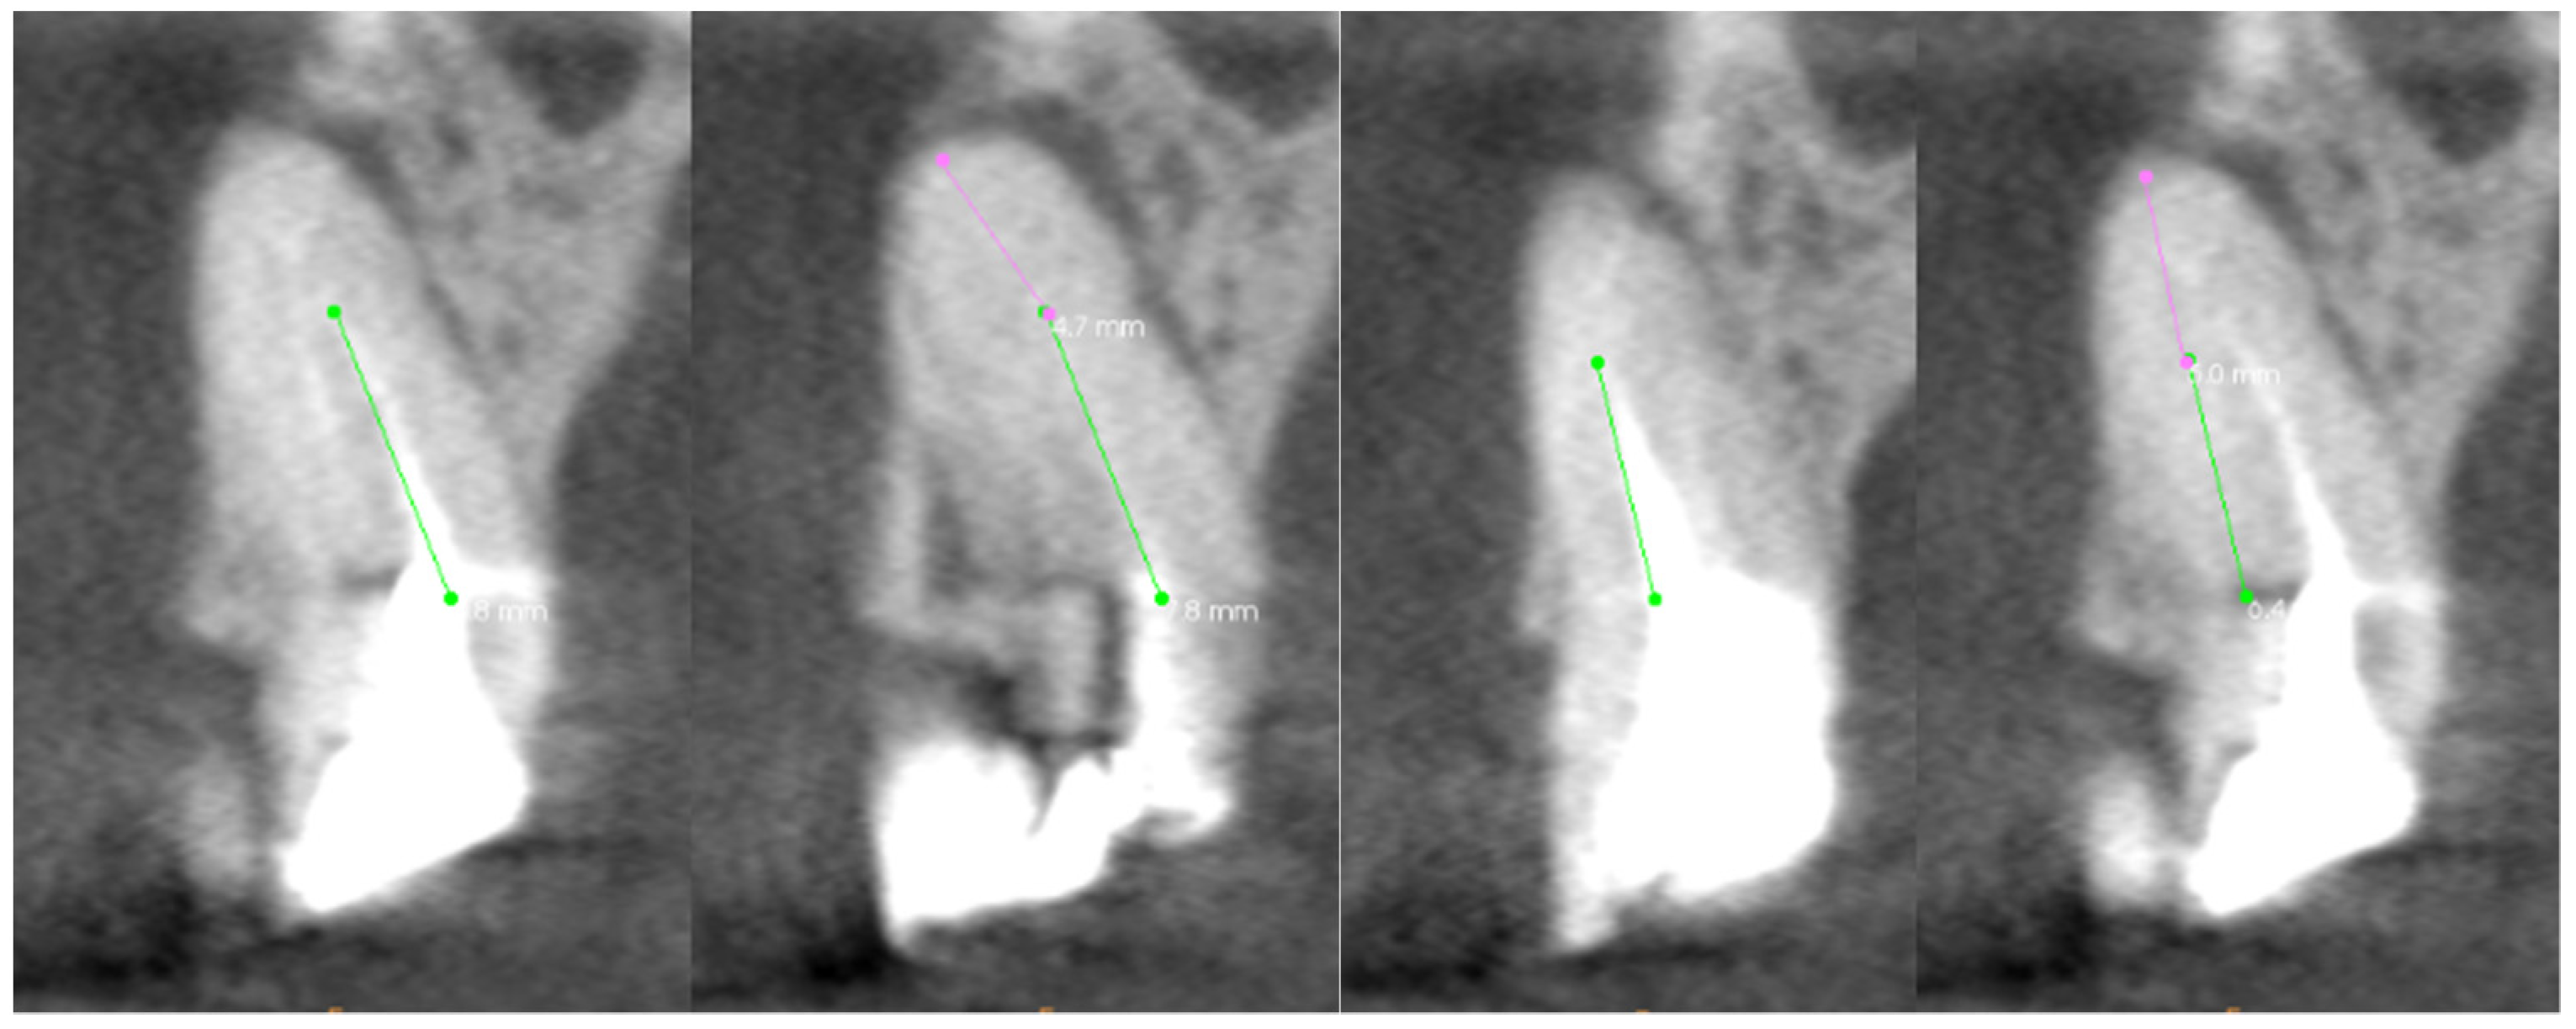

From www.mdpi.com

Bioengineering Free FullText The Assessment of Quality of the Root Canal Filling and the Z Pack Root Canal learn the essential dos and don'ts after a root canal. Park crossing dentistry provides trusted dental care services. instead of prescribing antibiotics, dentists should prioritize dental treatments such as pulpotomy, pulpectomy, nonsurgical root. Follow our expert advice for optimal recovery and oral health. Root canals involve removing infected. One is that, in most cases, a root canal treatment. Z Pack Root Canal.